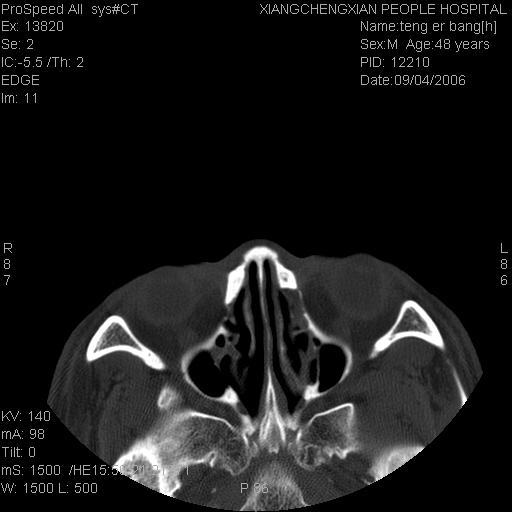

患者,男,以头面部外伤后头疼1小时为主诉入院,患者1小时前被他人打伤头部及左侧面部,眼睑无水肿,左侧面部肿胀压疼,未触及骨擦音。专科检查:耳鼻喉未见异常。

ct:平扫+冠扫:双侧鼻骨对比,冠扫s6#示右侧鼻骨尖部可见线状低密度影,边缘光滑,并见硬化.软组织未见肿胀.

诊断意见:鼻额缝(鼻骨与上颌骨额突缝),但个别同志认为是骨折.因此请同行们会诊.多谢了!

正常鼻颌缝。软组织无肿胀。鼻腔无积液积血。鼻骨光滑规整无中断。均不支持骨折。

正常鼻颌缝。软组织无肿胀。鼻腔无积液积血。鼻骨光滑规整双侧对称。均不支持骨折。